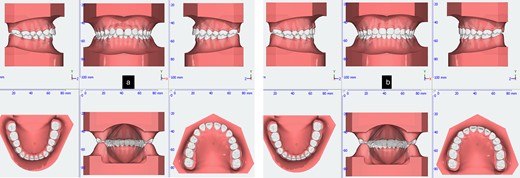

During the initial stage, orthodontic treatment was utilized to close the gaps between the teeth and move the upper and lower front teeth back using a fixed appliance, reverse curve wire, and power chain to achieve control tipping movement and improve her convex profile [6]. Tongue spurs were attached to keep the tongue in the correct position and prevent gaps from forming between the teeth. At the same time, a wire was used to intrude the upper front teeth during orthodontic treatment. The 3D simulation [7] before the treatment was done for consulting with patient and patient’s family (Fig. 2). The following procedures were performed: a fixed appliance was attached to both the upper and lower arches. Over a period of 4 months, alignment and levelling were done using a Niti wire, followed using a stainless-steel wire to close all the spaces using a sliding mechanic with reverse curve stainless steel wire bending on 0.017 × 0.025 SS and power chain. In the final 3 months, the detailing and finishing stage were completed to achieve functional occlusion (Fig. 3).

Tongue spurs bonding, alignment, leveling and space closure phase of the treatment.